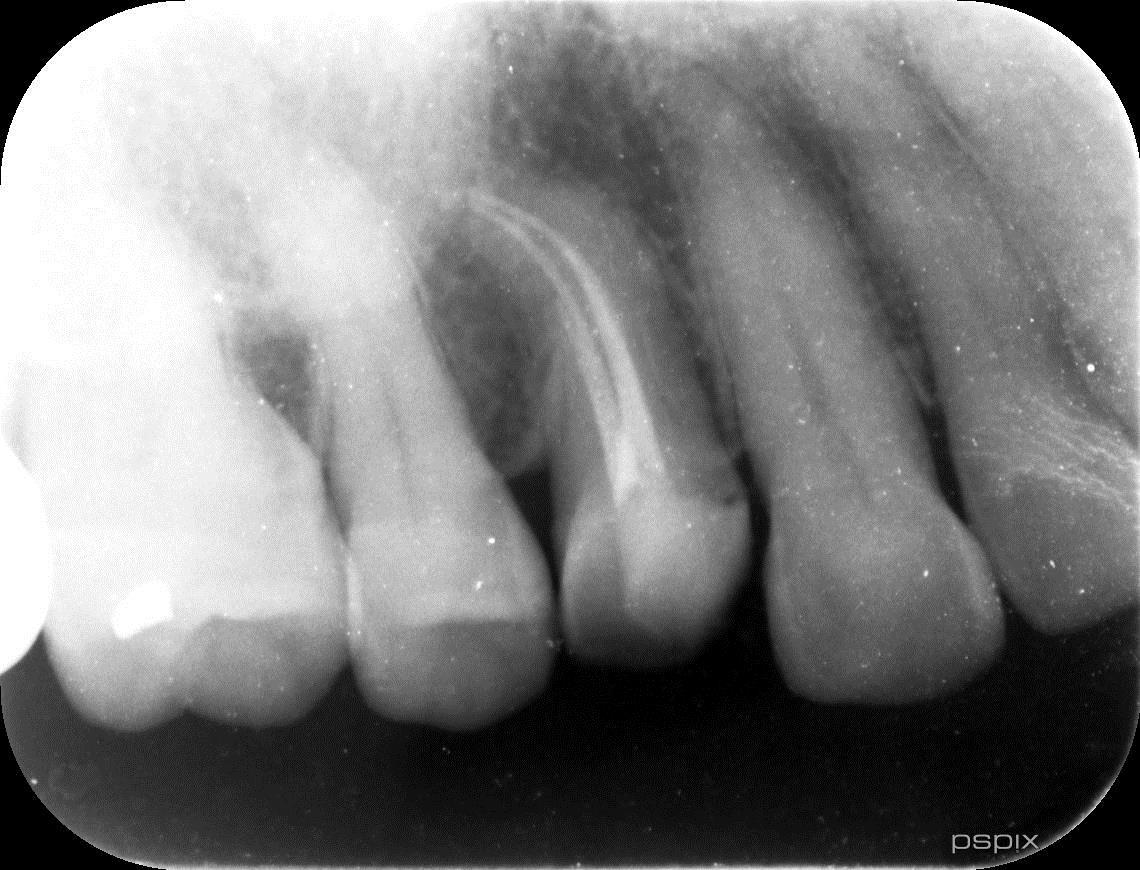

必要に応じてCT撮影を実施(根管形態の確認や病変の確認の為)

歯の根の形態は非常に複雑で、通常のレントゲンでは確認できない場合があります。CT撮影を行うことで、根管の本数や形、病変の広がりを立体的に把握し、的確な治療計画を立てます。